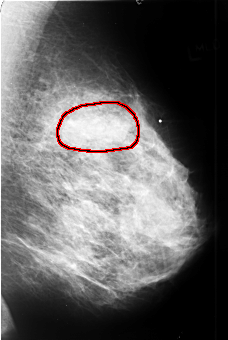

B_3409_1.LEFT_CC

LEFT_CC LINES 4456 PIXELS_PER_LINE 3000 BITS_PER_PIXEL 12 RESOLUTION 50 OVERLAY

FILE: B_3409_1.LEFT_CC.OVERLAY

TOTAL_ABNORMALITIES 1

ABNORMALITY 1

LESION_TYPE MASS SHAPE LOBULATED-IRREGULAR MARGINS OBSCURED-ILL_DEFINED

ASSESSMENT 4

SUBTLETY 4

PATHOLOGY MALIGNANT

TOTAL_OUTLINES 1

BOUNDARY